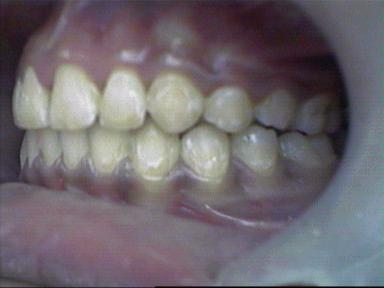

Before Treatment Intra Oral

After Treatment Intra Oral